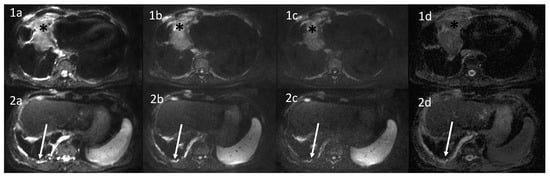

- Coolen, J.; De Keyzer, F.; Nafteux, P.; De Wever, W.; Dooms, C.; Vansteenkiste, J.; Derweduwen, A.; Roebben, I.; Verbeken, E.; De Leyn, P.; et al. Malignant Pleural Mesothelioma: Visual Assessment by Using Pleural Pointillism at Diffusion-weighted MR Imaging. Radiology 2015, 274, 576–584. [Google Scholar] [CrossRef] [Green Version]